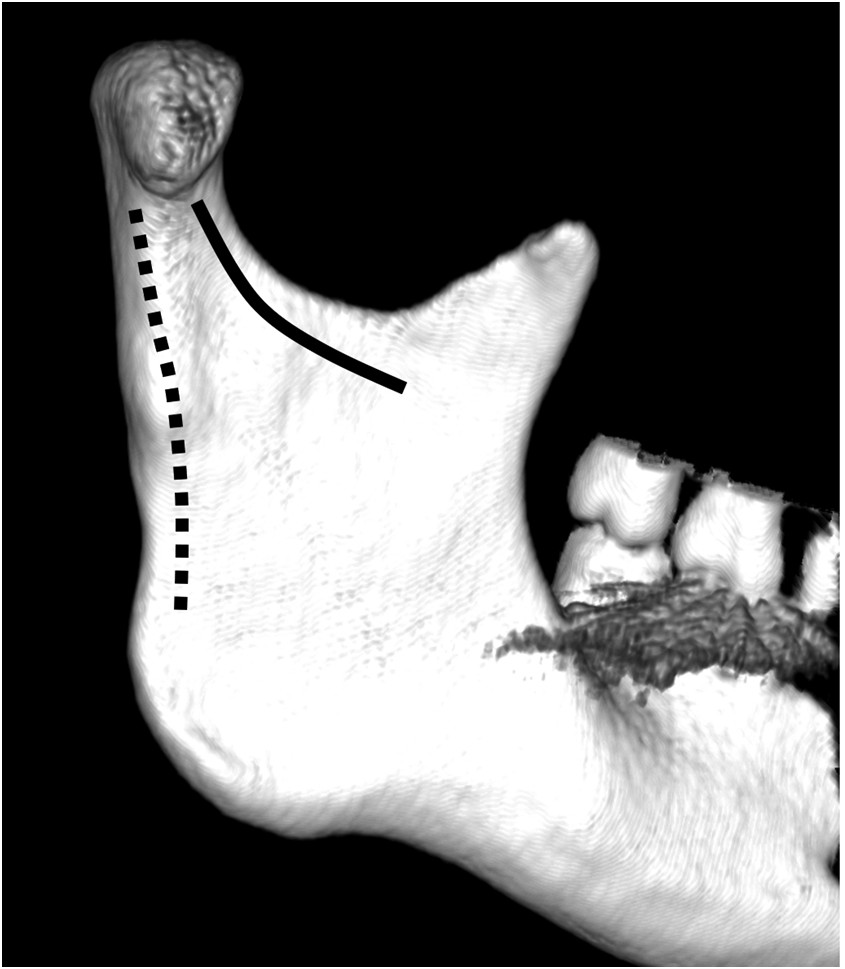

Pytanie 46

Budowa żuchwy jest przystosowana do przenoszenia obciążeń zgryzowych. Siła mięśni w czasie gryzienia powoduje naprężenia w wyrostku kłykciowym. Miejsca te zaznaczono 2 liniami (przerywaną i ciągłą). Wskaż prawdziwe stwierdzenie: